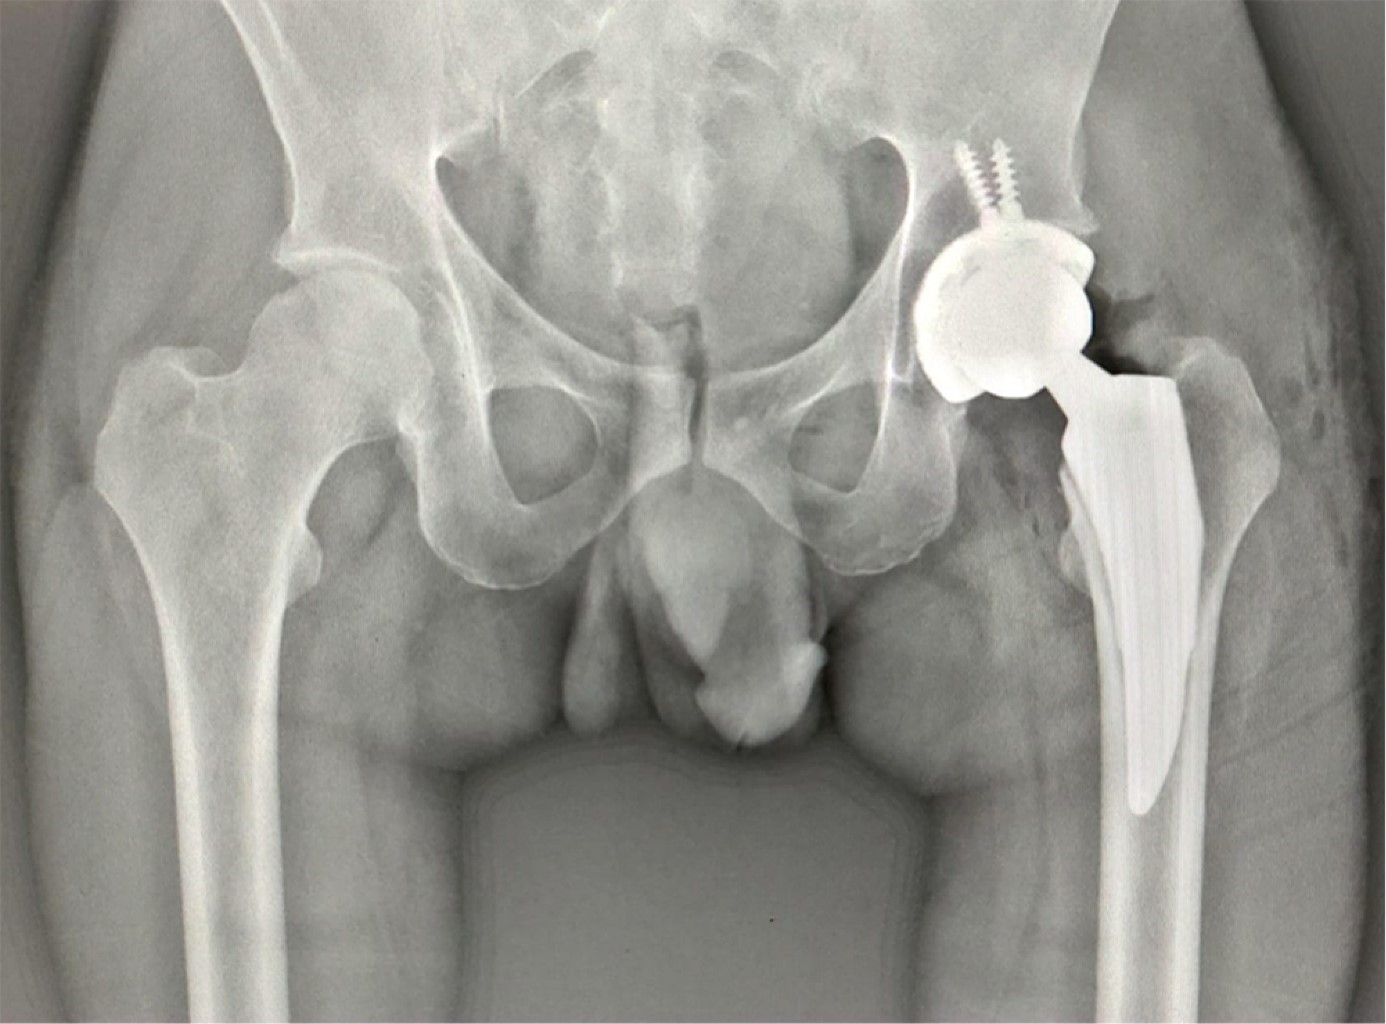

Figure 3